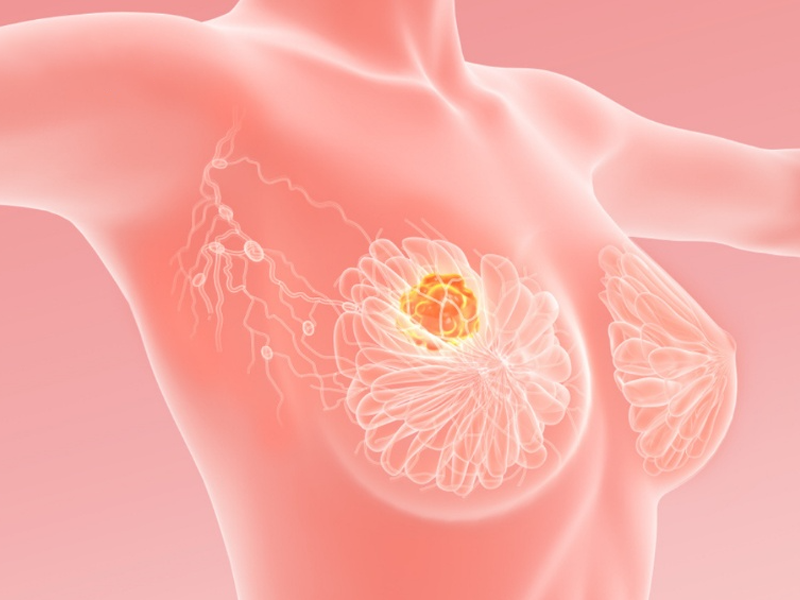

Bác sĩ Tuấn xác định đây là bướu sợi tuyến, một loại bướu lành tính của vú. Hiện bướu có kích thước to khiến bầu ngực đau và mất cân đối. Sau khi nghe bác sĩ tư vấn kỹ về bệnh, chị T. quyết định phẫu thuật bởi đã quá ám ảnh những cơn đau hàng tháng và cảm giác lo lắng khi mỗi lần sờ lên ngực phải.

Bác sĩ Đỗ Anh Tuấn cho biết bướu sợi tuyến (u xơ tuyến vú) là u lành tính ở vú, biểu hiện cục cứng, di động, thường gặp ở mọi lứa tuổi nhưng phổ biến ở phụ nữ từ 14 – 35 tuổi. Tỷ lệ mắc bướu sợi tuyến giảm khi tuổi càng cao. Ước tính, 10% dân số nữ trên thế giới mắc u xơ tuyến một lần trong đời.

Người bị bướu sợi tuyến có thể cảm thấy khối u ở trong vú. Khối u chắc, có giới hạn rõ ràng, di động. Với các bướu sợi tuyến nhỏ hơn 2cm, người bệnh không đau thì không cần điều trị, chỉ cần tái khám định kỳ.

Với bướu có kích thước lớn, người bệnh có thể lựa chọn phẫu thuật lấy khối u. Tuy nhiên, sau khi lấy khối u, đặc biệt là u vú có kích thước lớn vú có thể bị lõm, móp méo, sẹo xấu. Do đó, người bệnh cần được phẫu thuật tại cơ sở y tế có trang thiết bị hiện đại và bác sĩ có tay nghề cao, nhiều kinh nghiệm để đảm bảo an toàn và thẩm mỹ.

Bác sĩ Đỗ Anh Tuấn cảnh báo, bướu sợi tuyến có thể bị nhầm lẫn với: u nang vú, ung thư vú, u diệp thể, u lymphôm vú. Do đó, khi có khối u trong vú, người bệnh nên khám bác sĩ để được chỉ định làm các xét nghiệm kiểm tra, tầm soát và có hướng dẫn theo dõi hoặc điều trị thích hợp.